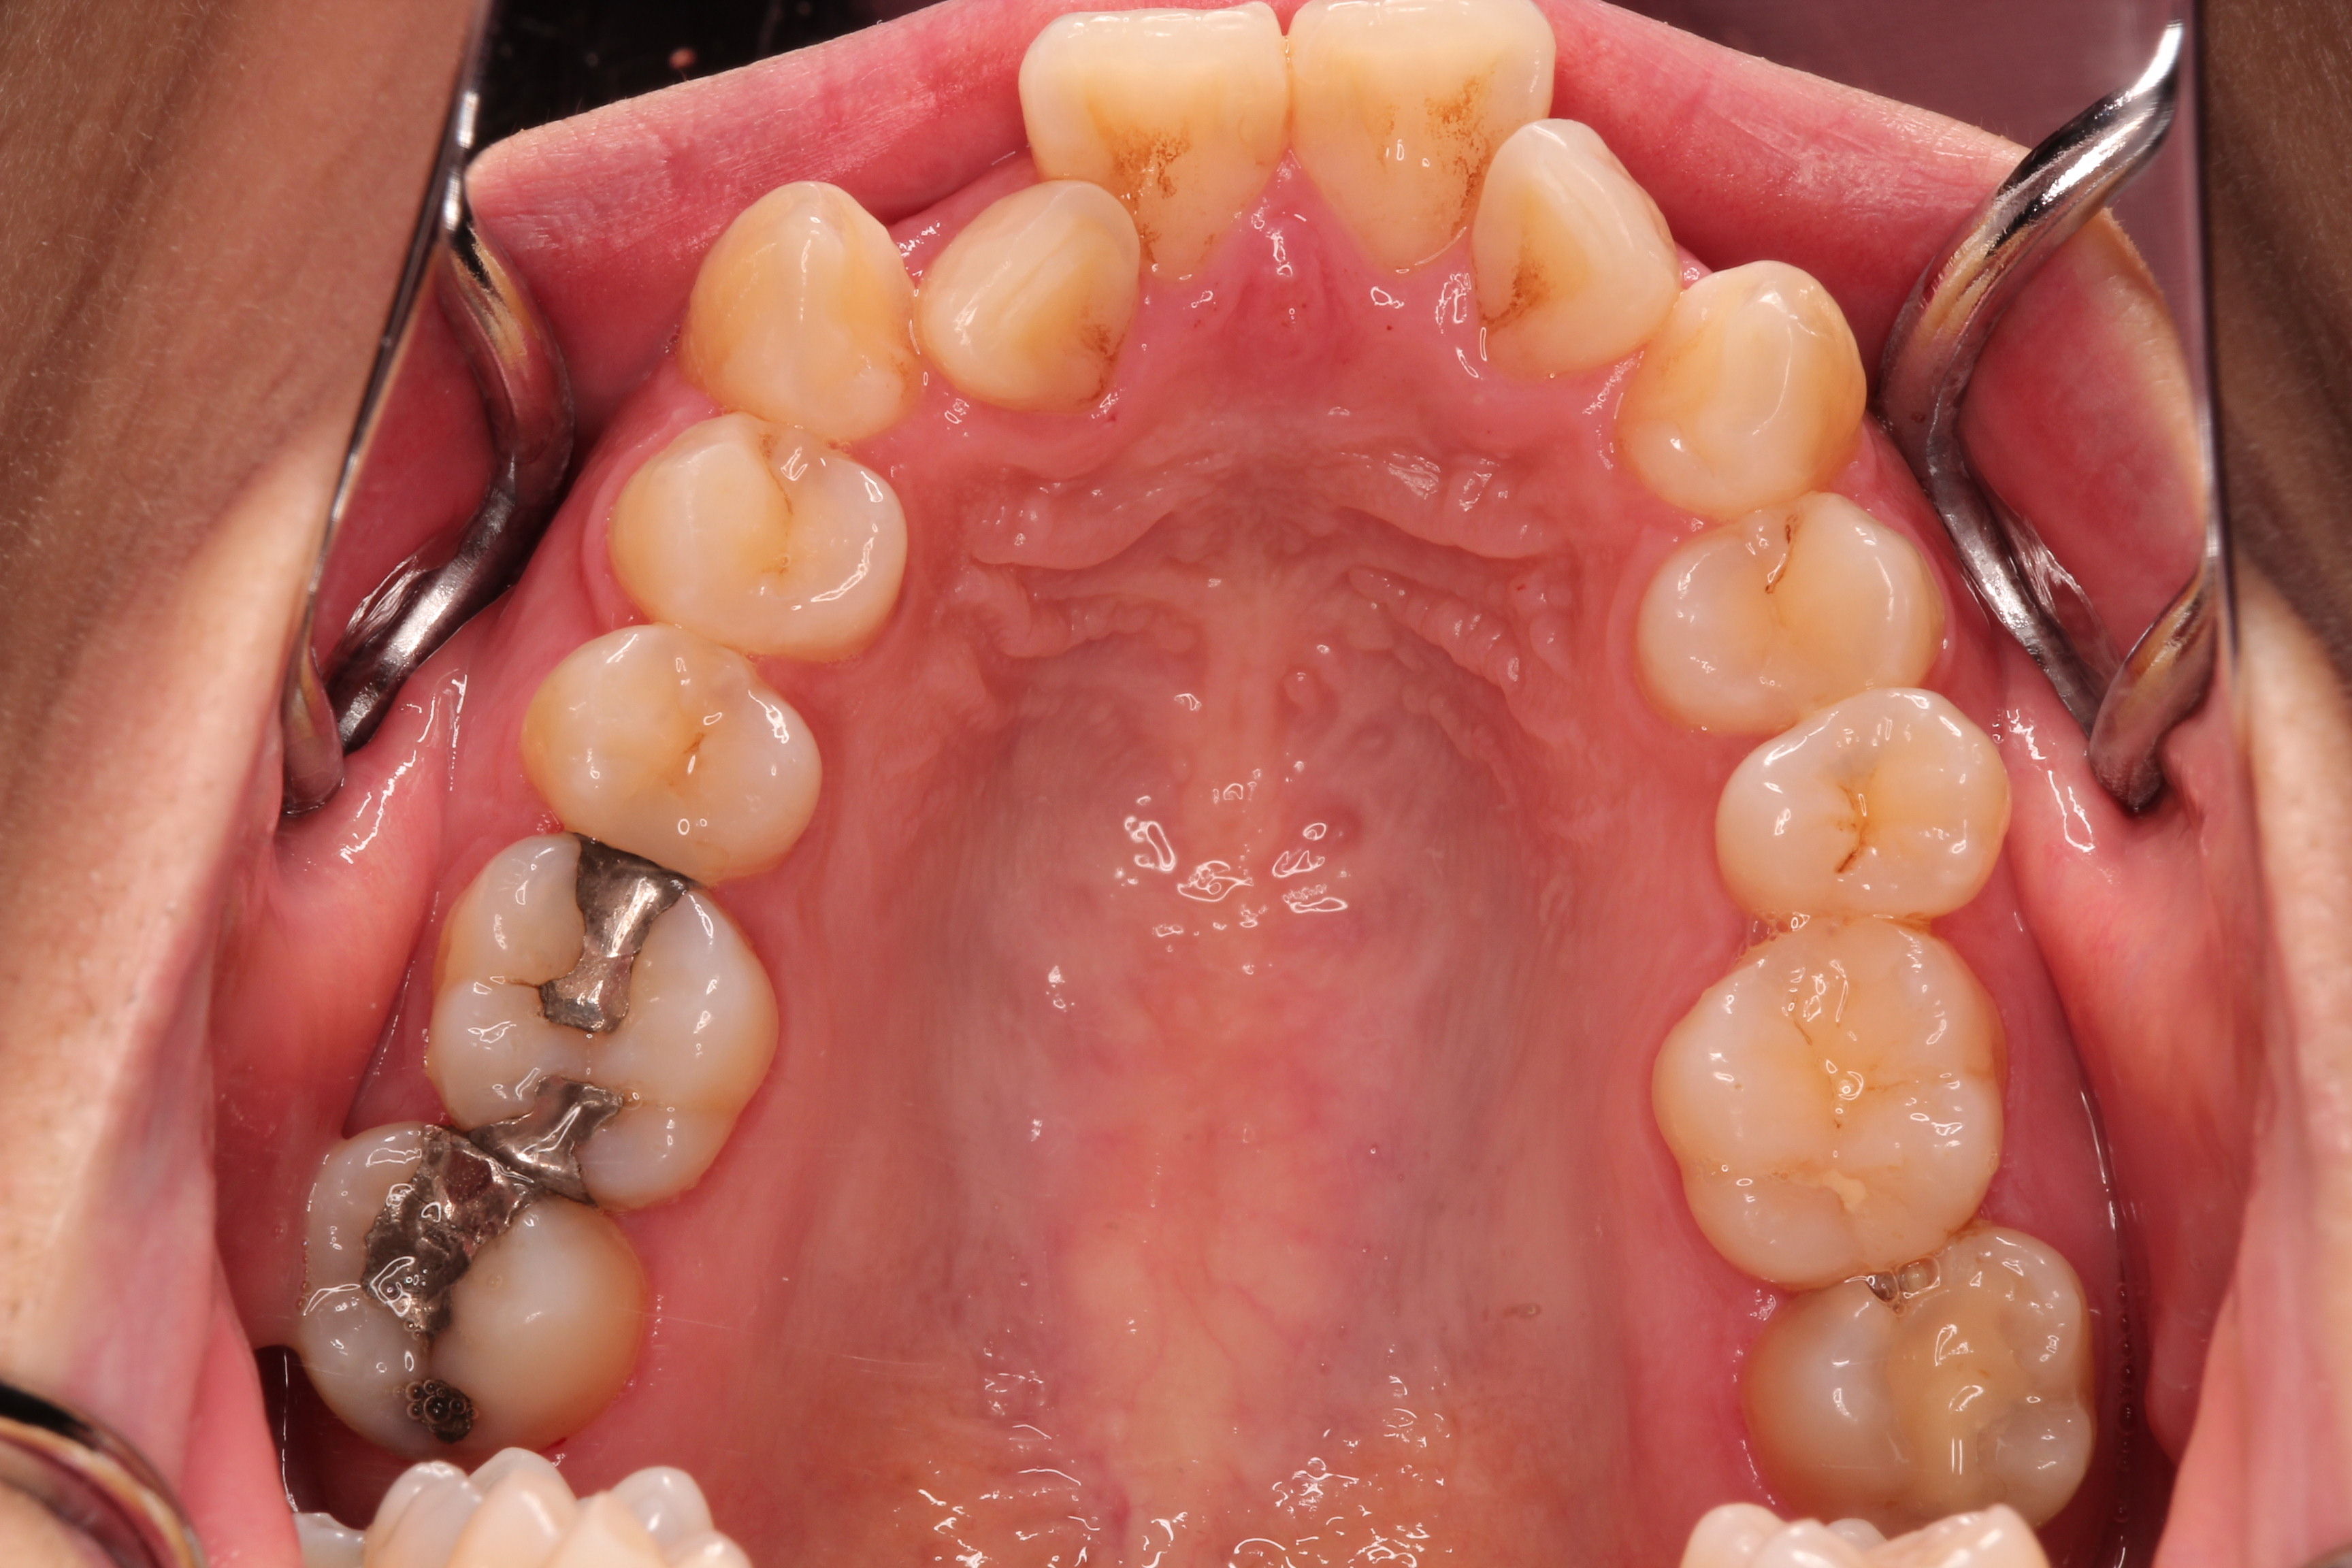

さて、今日はアマルガムについて書きたいと思います。

・・ですが、よしなか歯科クリニックでは使用しておりませんし、おそらく日本でも取り扱う歯科医院も少なくなってきていると思います。

この理由の大きな一つとして、大学の実習でも教えられなくなっているということがあります。

私は行いましたが、クリニック内の私を除いた先生らはやっていないと思います。

そのため、取り扱いということ自体がまず廃れてきたということがあります。

別の理由として、金属色が好まれなくなってきたということもあるでしょう。

またその他の理由として、下でも書く“水銀”というキーワードで敬遠される方が多いということもあります。

そして、代価の材料が開発され、その性状も向上しているということもあります。

アマルガムとは、銀や錫(すず)、銅、亜鉛の粉末を常温で液体金属である水銀と

混ぜ合わせることで化学反応がおき、結晶化したものです。

アマルガムを推奨される先生もおられ、利点もあることはあります。

その点も理解した上で使用するか、使用しないかということを決定していくべきであると思います。

少しこのあたりを掘り下げていきたいと思います。